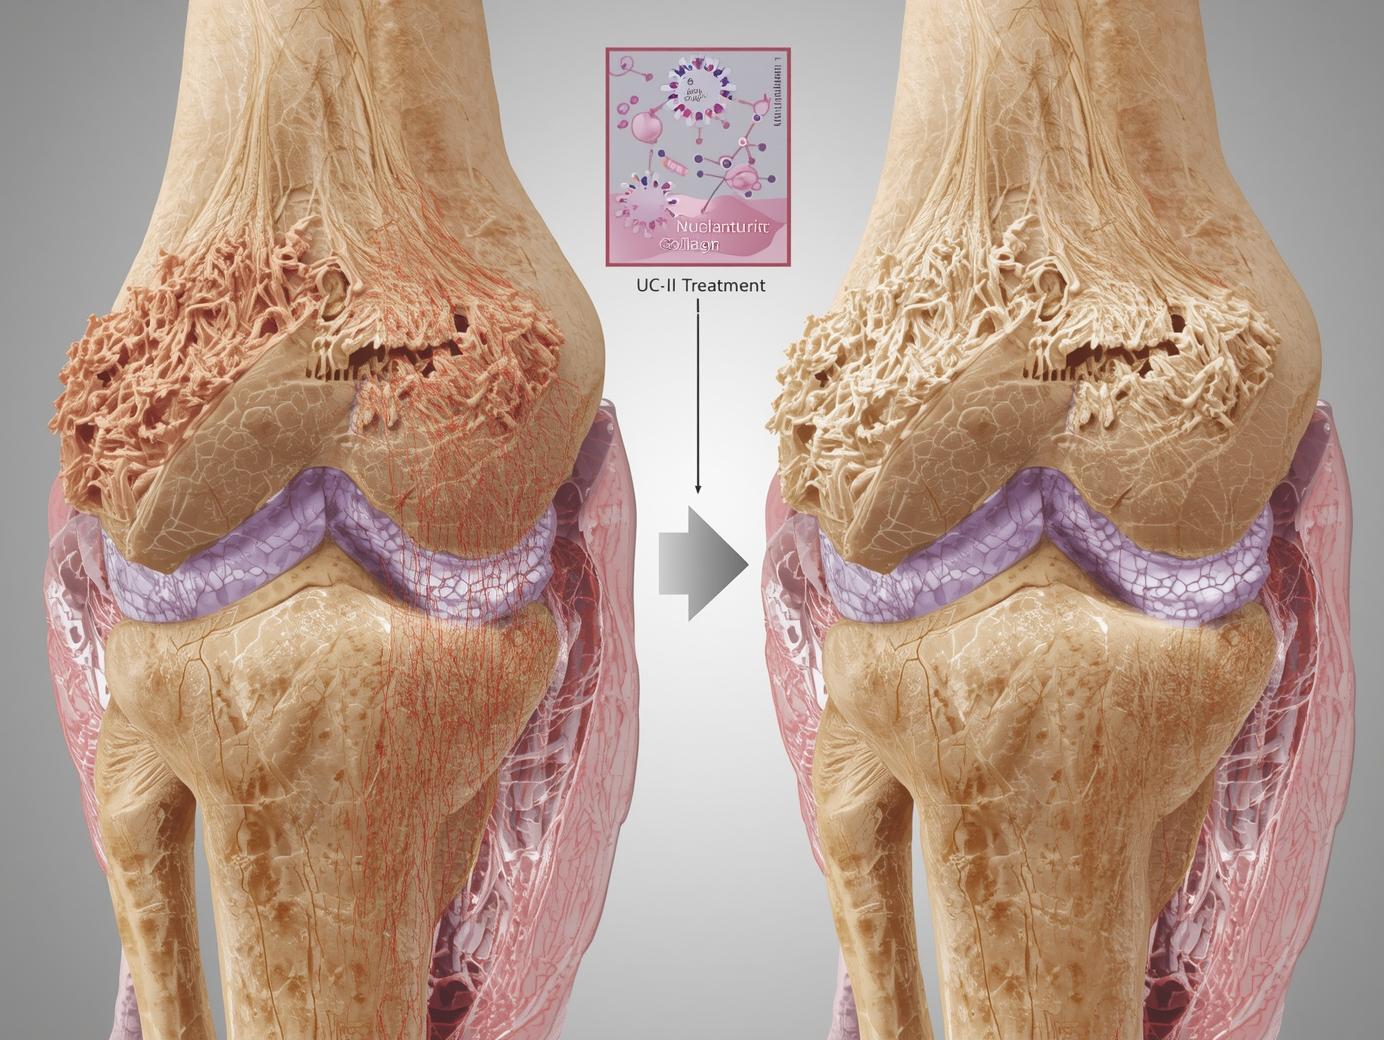

ایمنی و اثربخشی کلاژن آندینیچرد تایپ 2 (UC-II) در درمان استئوآرتریت زانو

استئوآرتریت (OA)یا آرتروز یکی از شایعترین انواع آرتریت است که میلیونها نفر را در سراسر جهان تحت تأثیر قرار میدهد و باعث درد، سفتی و کاهش کیفیت زندگی میشود. درمانهای فعلی عمدتاً علائم را تسکین میدهند و بیماری را معکوس نمیکنند. کلاژن آندینیچرد تایپ 2 (UC-II) که از جناغ سینه مرغ استخراج میشود، در مطالعات قبلی نشان داده است که میتواند در درمان آرتریت روماتوئید (RA) مؤثر باشد. این مطالعه به بررسی ایمنی و اثربخشی UC-II در مقایسه با ترکیب گلوکوزامین و کندرویتین (G+C) در درمان آرتروز زانو پرداخته است.

مصرف روزانه 40 میلیگرم UC-II به مدت 90 روز منجر به بهبود معنادار در درد، سفتی و عملکرد فیزیکی بیماران مبتلا به آرتروز زانو شد و اثربخشی آن بهطور قابل توجهی بالاتر از ترکیب گلوکوزامین و کندرویتین بود. همچنین، UC-II ایمنی خوبی داشت و عوارض جانبی کمتری نشان داد. این مطالعه نشان میدهد که UC-II میتواند بهعنوان یک گزینه درمانی مؤثر و ایمن برای بیماران مبتلا به آرتروز زانو مورد استفاده قرار گیرد.

- درمان آرتروز: UC-II میتواند بهعنوان یک مکمل طبیعی برای کاهش درد و بهبود عملکرد مفاصل در بیماران مبتلا به آرتروز استفاده شود.